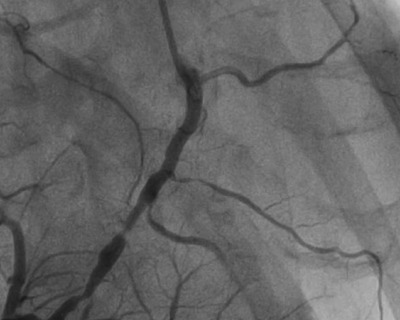

A coronary angiogram is an imaging test that uses X-rays to see the inside of the coronary arteries. It involves injecting a contrast dye into the blood vessels of the heart to make them visible on the X-ray images. A Coronary Angiogram Test in Hyderabad helps in diagnosing heart conditions and determining the severity of blockages in the arteries.

- Contrast Dye Injection: A contrast dye is injected through the catheter to highlight the coronary arteries.

- Imaging: X-ray images are taken as the dye moves through the arteries.